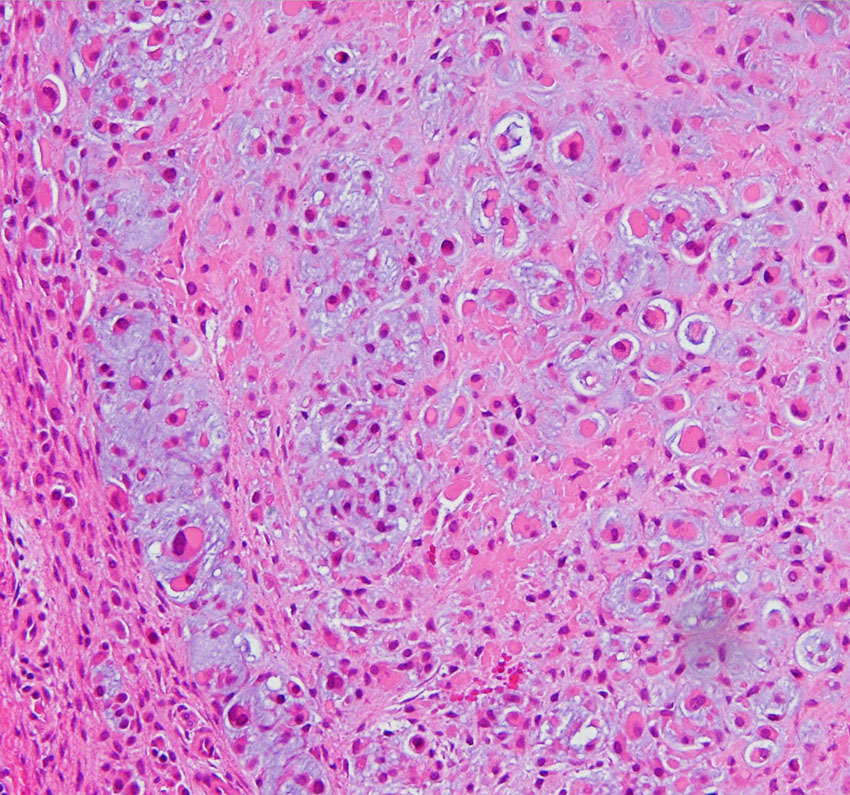

低悪性度軟骨肉腫の病理像 grade 2 chondrosarcoma

背景は好塩基性の軟骨基質(粘液状 myxoid,軟骨様 chondroid)です。好酸性胞体をもつ異型紡錘形ないし上皮様細胞が多結節状に増殖しています。細胞密度はやや高い部分もあり,核は濃縮され大小不同や2核の細胞も見られます。MIB-1 index 3%